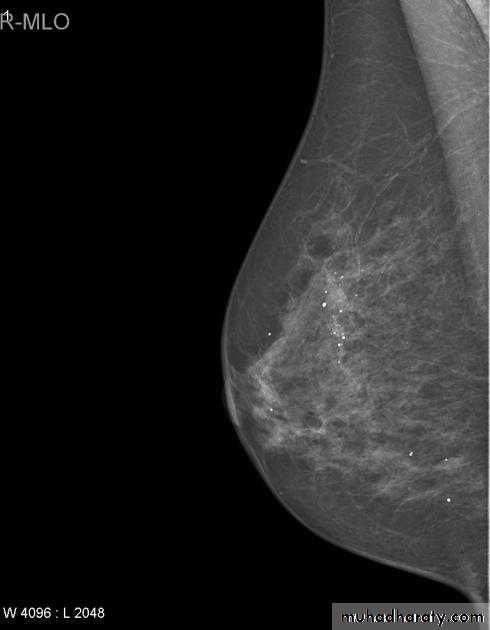

Infiltrating or invasive lobular carcinoma (ILC) of the breast is the second most common type of invasive breast cancer after invasive ductal carcinoma (IDC) .

Radiographic features

ILC is more often multicentric and bilateral (10-15%). Therefore imaging evaluation of the contralateral breast is crucial. There can be very subtle changes such as progressive shrinkage or enlargement or reduced compressibility of the involved breast. Imaging often underestimates the disease.

Mammography

The sensitivity of mammography for the detection of ILC reportedly ranges between 55-80% 8. Because of the limitations of mammography in detecting ILC, other modalities, such as sonography and MR imaging, are being used in evaluating clinically suspicious findings and known cancers to assess the extent of disease. ILC are more commonly seen on the craniocaudal (CC), compared to the mediolateral oblique (MLO).